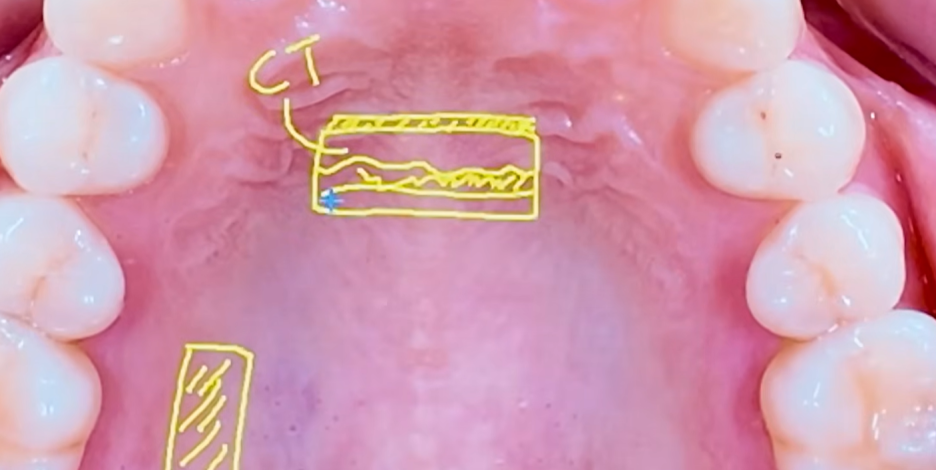

결합조직 이식술은

잇몸이 내려간 부위에 본인의 잇몸 조직을 이식해 보강하는 치료를 말해요.

보통 입천장 쪽의 결합조직을 일부 잘라내어

잇몸이 얇아지거나 내려간 부위에 옮겨 심고 이식하는 방식이예요.

이를 통해 잇몸 두께를 보강하고

노출된 치아 뿌리를 덮는 것을 목표로 합니다.

1.CTG 결합조직이식술

출처 - 권의시선 : 치과의사 권낙현 유튜브  CTG(결합조직이식술)-입천장에서 결합조직을 채취하여 내려앉은 잇몸에 이식하는 치료방식

출처 - 권의시선 : 치과의사 권낙현 유튜브  입천장에서 채취한 조직을 내려앉은 부위에 붙인 모습.